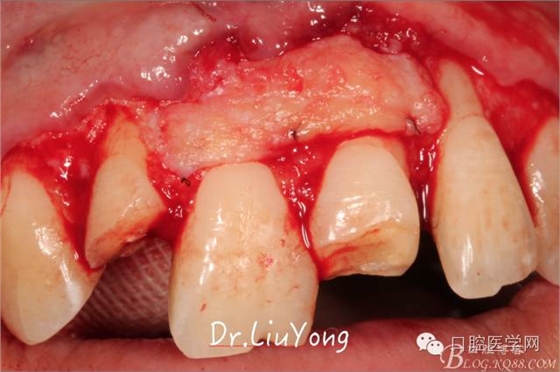

A區(qū)腭側(cè)所移取的上皮下結(jié)締組織瓣,如上圖

將結(jié)締組織瓣縫合固定于受區(qū),如上圖